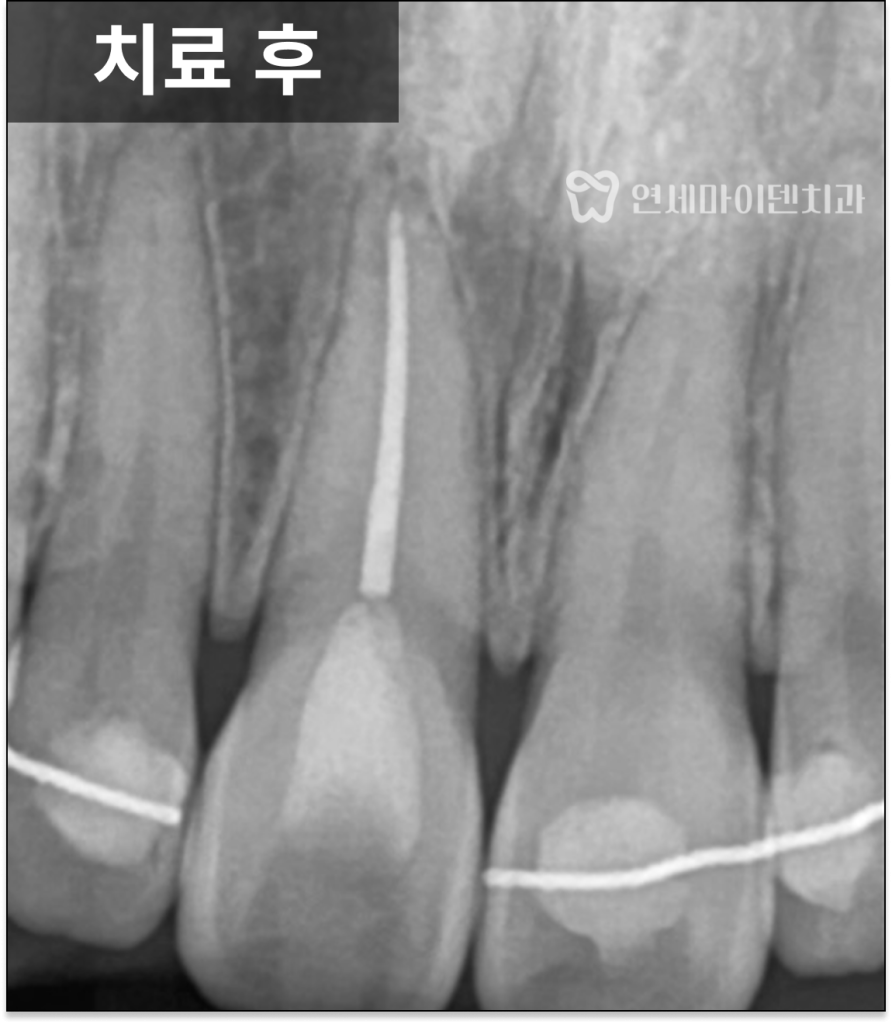

변색을 개선하기 위해

치아 내부에 미백제를 적용하는

실활치 미백을 진행했고,

1~2주 경과 후

색이 자연스럽게 회복된 것을 확인한 뒤

레진으로 마무리했습니다.

적절한 위치에서 신경관 충전 재료를 정리하고

상부를 레진으로 안정적으로 접착하면

변색 재발도 충분히 줄일 수 있습니다.